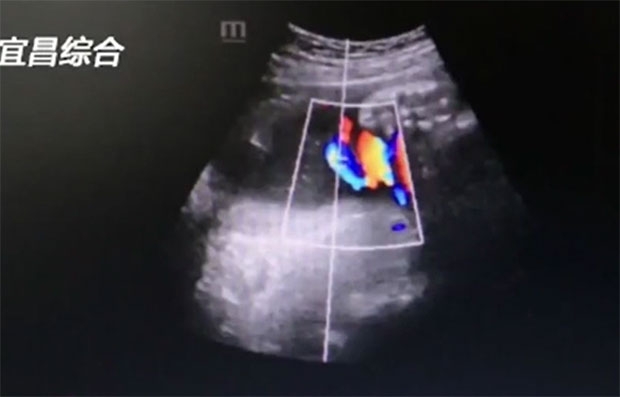

지난달 30일 후베이성 이창시의 한 병원 분만실에 산부인과 의사 여러 명이 우르르 몰려들었다. 목에 탯줄이 6바퀴나 감긴 아기가 살아서 태어난 것을 두 눈으로 확인하기 위해서였다. 산모는 “모든 의사가 아기를 보려고 몰려들었고, 탯줄이 몇 번이나 감겼는지 세어 보았다”라고 밝혔다.

의료진은 고심에 빠졌다. 계속 자연분만으로 출산을 진행하면 아기가 탯줄에 질식사할 우려가 있었다. 위험하긴 했으나 산모와 태아의 모든 수치가 정상 범위 안에 있었기에 의료진은 계획대로 자연분만을 계속했다.

그러나 탯줄을 6바퀴나 감고도 별 탈 없이 태어나는 아기는 흔치 않다. 담당의는 “23년 의사 생활 중 처음 본다”라며 기적에 가까운 일이라고 말했다. 걱정이 많았던 산모도 “문제없이 건강하게 태어나 다행”이라고 가슴을 쓸어내렸다. 그러면서 “아기가 배 속에서 어찌나 개구쟁이였는지 모른다”라고 웃음을 지어 보였다.